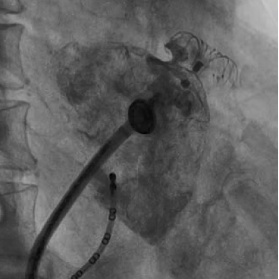

一个月后,肖方毅医师在心腔内超声和三维电解剖标测系统指导下为蔡老伯成功实行房颤射频消融联合左心耳封堵术。这是目前最新的技术,整个消融过程因为有心腔内超声的指引,无需任何射线,直视下精准构建左房模型,精准消融(图1)。消融后肖方毅医师用自己创立的“FLAVOR”术式,在腔内超声指导下顺利植入左心耳封堵器(图2,图3),避免了以往术中需要做经食道心超检查的痛苦。

图3:DSA下造影见封堵器完全封堵左心耳